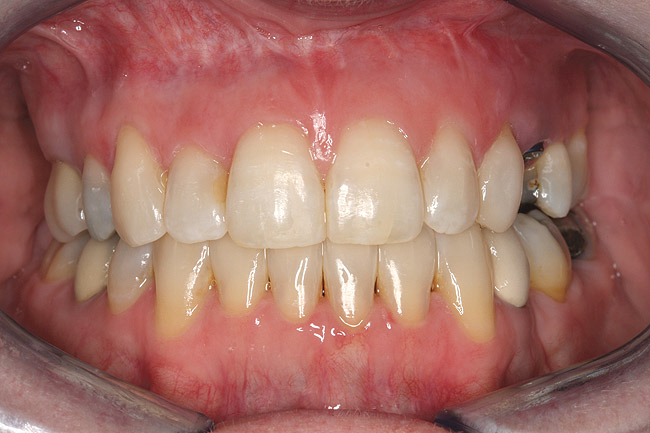

Fig 16 (and Fig 17). Anterior deep bite with extruded and retruded anterior dentition secondary to unstable relationship.

Figure 16

Fig 17 (and Fig 16). Anterior deep bite with extruded and retruded anterior dentition secondary to unstable relationship.

Fig 21 (and Fig 20). There is significant lateral dentoalveolar expansion of arches and alveoloskeletal correction in maxillary and mandibular anterior regions. Alveolar bone volume was increased in lower anterior to create optimal implant sites and establish ideal interincisal function and stability.